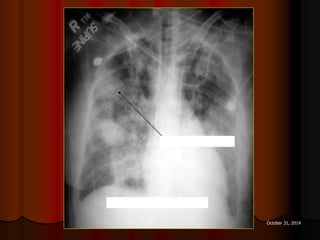

NHÖÕNG BOÙNG DAÏNG HANG

AÙP-XE THUØY TREÂN PHOÅI (P)

AÙP-XE THUØY TREÂN PHOÅI (T)

AÙP-XE THUØY LÖÔÕI PHOÅI (T)

AÙP-XE PHOÅI

HANG LAO